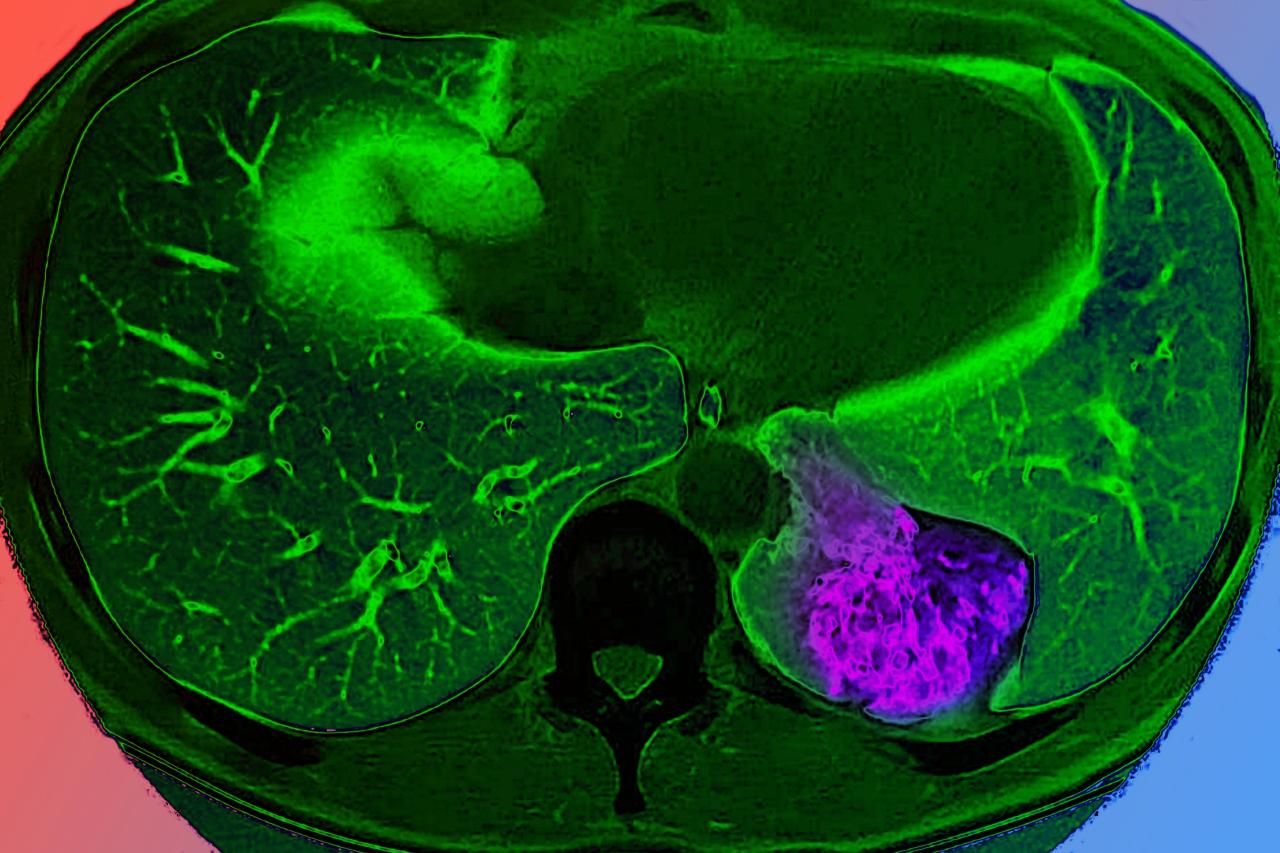

A tüdőrák évtizedek óta csak a kontrollt vesztett sejtosztódás hibájaként szerepelt az orvosi gondolkodásban, de friss kutatások feltárták: a daganatok aktívan kommunikálnak az aggyal, hogy kijátsszák az immunrendszert. Ezek az eredmények nemcsak a rák megértésében jelentenek fordulópontot, de új terápiás lehetőségeket is felvillantottak.

A kutatók már régóta tudják, hogy bizonyos daganatokba idegek nőnek be, és a sok ideget tartalmazó tumorok rosszabb kimenetellel járnak. Most először sikerült igazolni, hogy ezek az idegek nem csupán közvetlen környezetükben hatnak: a tüdődaganat a bolygóidegen (nervus vagus) keresztül információt juttat el az agytörzsbe, mégpedig a magányos pálya magjába, amely normális esetben az életfontosságú szervek működését – például a vérnyomást vagy az emésztést – hangolja össze.

A daganat ezt az idegpályát kihasználva olyan impulzusokat küld az agynak, amelyek hatására a szimpatikus idegrendszert aktiválja – ezt ismerjük az üss vagy fuss mechanizmus motorjaként. Ennek következtében jelentős mennyiségű noradrenalin szabadul fel közvetlenül a tumor környezetében. Ez a hormon általában az immunrendszer első számú védősejtjein, a makrofágokon hat, amelyek felületén speciális, adrenerg receptorok találhatók.

Sőt, amikor a noradrenalin ezekhez a receptorokhoz kapcsolódik, a makrofágok szó szerint oldalt váltanak: helyreállító, a daganatot nem támadó üzemmódba kapcsolnak, és olyan vegyületeket termelnek, amelyek passzivitásra intik az egész immunrendszert.

Például a legfontosabb tumorellenes sejtek, a T-sejtek így elveszítik harci kedvüket és felismerőképességüket. A daganat egy komplett védekezőpajzsot húz maga köré, amely semlegesíti a test leghatékonyabb védekezőmechanizmusait.

Ugyanakkor a kutatók felfedezték, hogy a daganat és agy közötti kommunikáció megszakítása újraindítja az immunválaszt. Bár ezek az eredmények egyelőre egérmodelleken alapulnak, a daganat–ideg–agy kör leállítása mindenhol hatásosnak bizonyult. Ez áttörő lehetőséget teremt a jövő daganatellenes kezeléseihez, habár az egérről emberre történő átültetés még további kutatásokat igényel.